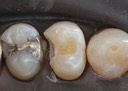

Joe Cha #18 pre-cementation

Joe Cha #18 finish